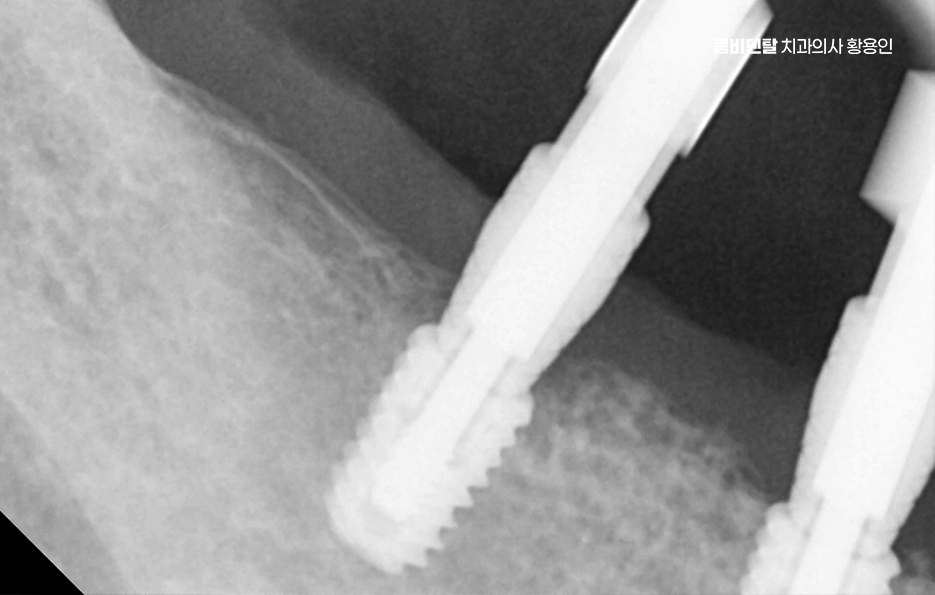

또 치아가 없어진 자리는 잇몸 뼈가 점점 흡수되면서 꺼지게 되는데, 그 결과 얼굴이 비대칭으로 보이거나 추후에는 임플란트를 하려고 해도 부족한 잇몸 뼈로 인해 뼈이식과 같은 치료를 추가적으로 받아야 할 수 있었어요

치아 발치 후 임플란트 치료 과정을 살펴보면 임플란트는 티타늄이라는 재료로 만든 인공 치근을 잇몸 뼈에 식립하고, 그 위에 보철물을 올리는 구조로 티타늄은 인체에 잘 맞는 재료라 뼈와 자연스럽게 붙는 성질이 있는데 이 과정을 ‘골융합’이라고 하고 이 골융합이 안정적으로 일어나야만 임플란트가 오래 버틸 수 있고, 자연치아처럼 역할을 할 수 있는 거예요.

치아 발치 후 임플란트 치료 과정은 처음에 CT나 파노라마 엑스레이를 통해 뼈의 양과 밀도, 신경 위치를 정확히 확인하는 것부터 시작되며 치아가 빠진 자리에 뼈가 많이 흡수되어 있다면, 임플란트를 심기 전에 뼈이식을 먼저 해야 할 수 있지만 반대로 뼈 상태가 좋다면 임플란트를 심고, 보통 3개월 동안 뼈와 잘 붙을 때까지 골융합 과정을 기다리게 되며 골융합이 잘 이루어진 뒤에는 그 위에 지대주라는 연결 부품을 끼우고, 그 위에 최종 보철물을 씌우면서 치료가 마무리되고 있어요